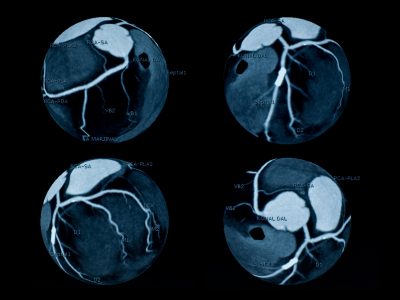

Процедура рентгеновского кровеносных сосудов в сердце. Краска вводится в сосуд с помощью катетера, который позволяет кровеносным сосудам быть визуализированы. Эта процедура может определить завалов и других проблем, препятствующих с потоком крови.